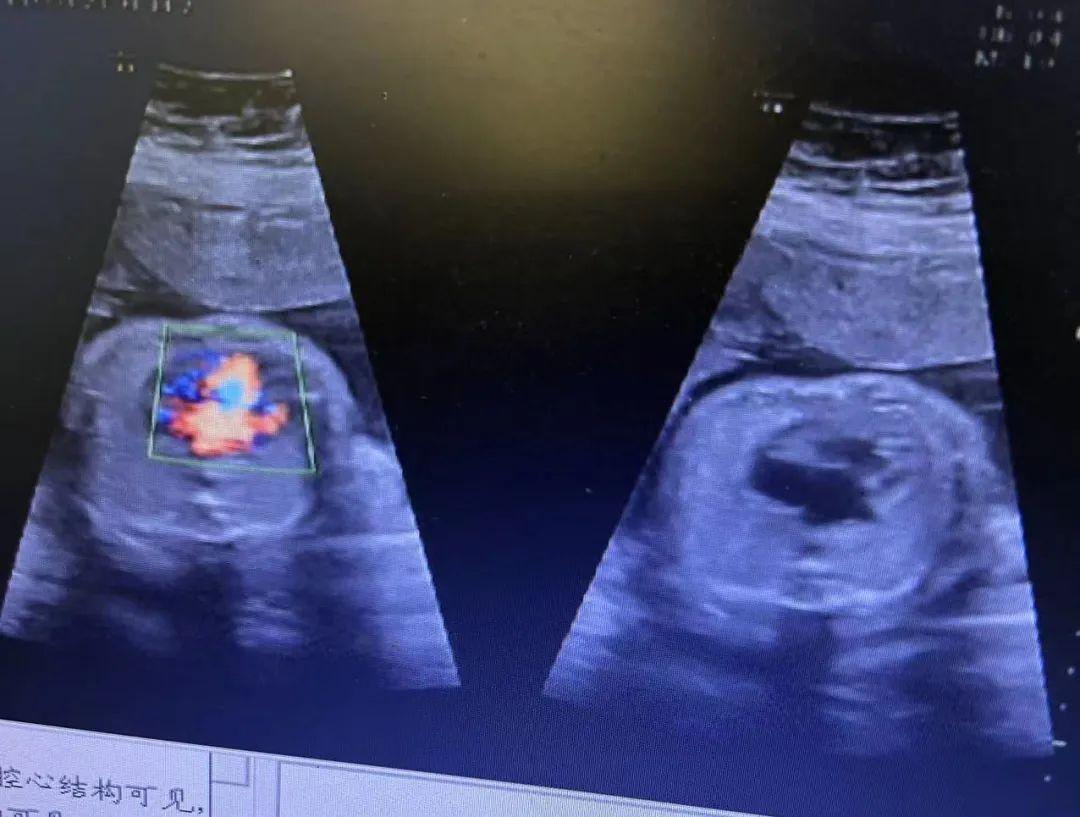

近日,武漢仁愛(ài)醫(yī)院收治了一例特殊的女患者。停經(jīng)數(shù)月才來(lái)醫(yī)院就診,發(fā)現(xiàn)自己懷孕,且經(jīng)過(guò)四維彩超產(chǎn)檢發(fā)現(xiàn)腹中胎兒心臟畸形。武漢仁愛(ài)醫(yī)院超聲科王娟主任介紹,由于該患者有多囊卵巢疾病病史,導(dǎo)致體態(tài)肥胖,足足有220斤,所以懷孕了都渾然不知,因停經(jīng)數(shù)月才想到來(lái)醫(yī)院看診,經(jīng)過(guò)檢查才發(fā)現(xiàn)自己已經(jīng)懷孕24周。

近日,我院超聲科醫(yī)生在給孕中期孕媽做四維彩超檢查時(shí),發(fā)現(xiàn)胎兒查出異常,孕媽想留下這個(gè)寶寶,陷入了兩難。

武漢的劉女士(化名),前幾個(gè)月剛懷上寶寶,全家都特別高興。懷孕23周+時(shí),劉女士在家人的陪伴下來(lái)到武漢仁愛(ài)醫(yī)院超聲科做了四維彩超檢查,當(dāng)醫(yī)生拿出檢查報(bào)告的時(shí)候,劉女士卻當(dāng)場(chǎng)傻眼了,原來(lái),在四維彩超的報(bào)告里,診斷出了胎兒右肺囊性腺瘤樣病變,她的心頓時(shí)揪了起來(lái)!

劉女士看到檢查結(jié)果后,擔(dān)心該病變會(huì)影響腹中寶寶的健康,考慮是否應(yīng)該終止妊娠。隨即,武漢仁愛(ài)醫(yī)院超聲科王娟主任為劉女士耐心地解釋:“先天性肺囊腺瘤是一種肺組織錯(cuò)構(gòu)畸形,先天性肺囊腺瘤畸形病例約70%的腫塊大小較穩(wěn)定;約20%腫塊產(chǎn)前明顯縮小或消失;僅10%腫塊是進(jìn)行性增大。單純的先天性肺囊腺瘤(CCAM)無(wú)水腫的胎兒可以密切隨訪,在28周前接受連續(xù)超聲復(fù)查,CVR<1.6,一般超聲動(dòng)態(tài)監(jiān)測(cè)2~4周監(jiān)測(cè)一次,而對(duì)于CVR≥1.6的需要在28周前每周1-2次的超聲監(jiān)測(cè),防止出現(xiàn)胎兒水腫,直到分娩。”